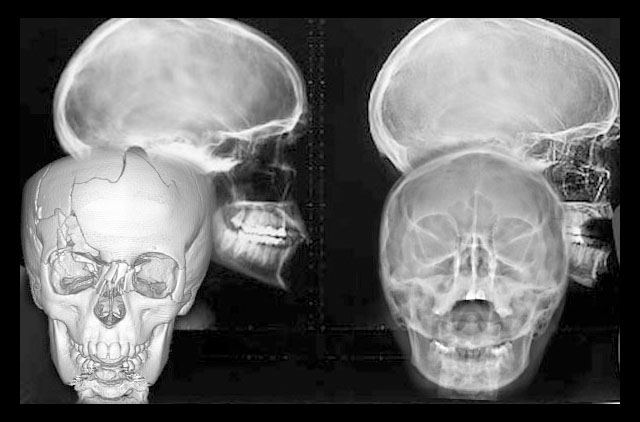

Tomografía 3D (Disponible en sucursal Guelatao y Roma)

La diferencia radical entre la tomografia cone-beam (TCB) y la tomografia computarizada (TC) es la forma de procesar la imagen, es decir la TC es generada a partir de imagenes 2D en la cual se producen aberraciones o distorsiones, sin poder usarla con un poder fidedigno, en cambio la TCB la reconstruccion se hace a través de cortes, sin provocar distorsiones, deja una escala 1:1.

Estudio completo de ortodoncia en 3D (cone-beam) digital CD

-Trazos Cefalométricos, tomografía volumétrica cone-beam